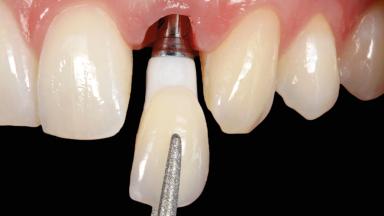

In this case, Arndt Happe describes how he achieved a stable outcome at 5 years by giving careful attention to the coronal aspect of the transmucosal area of the provisional, creating a slim emergence profile.

A healthy 31-year-old female patient presented with a failing maxillary left lateral incisor crown. The crown regularly loosened, and the remaining tooth was neither restorable nor rational to treat. The patient had a high smile line, a medium soft tissue biotype with a compromised mesial papilla (shorter than the contralateral one), and a horizontal scar in the buccal soft tissue as a result of past periapical surgery.